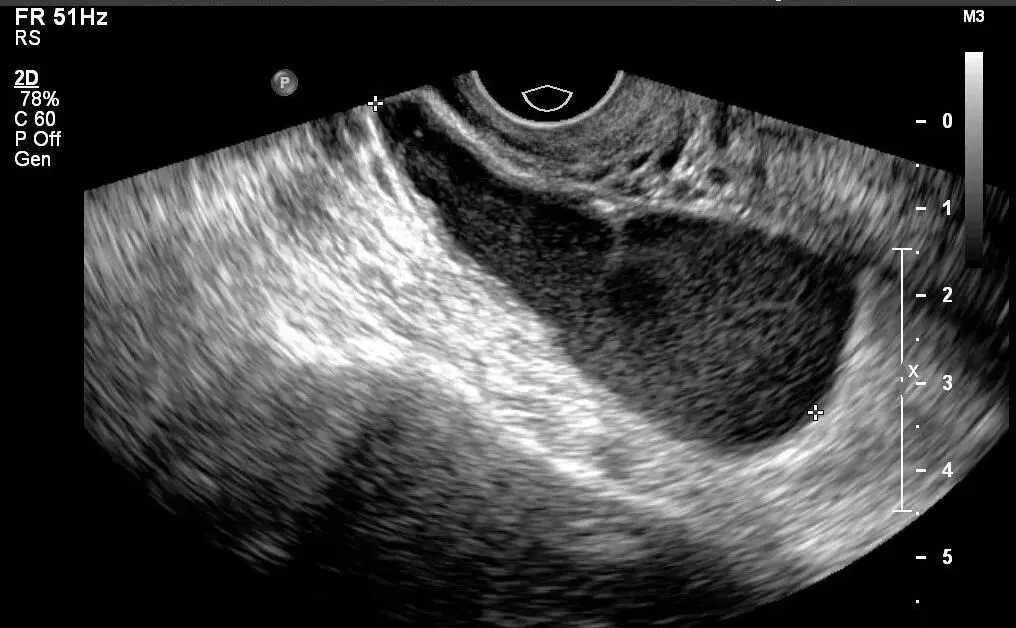

●宫内节育器位置正常:节育器强回声位于宫腔中心,其周围内膜显示为低回声的晕圈。在子宫纵切面可判断宫内节育器在宫腔内的位置正常位置的宫内节育器应全部位于宫腔内,且节育器最下缘不低于宫颈内口。

宫内节育器位置异常声像图